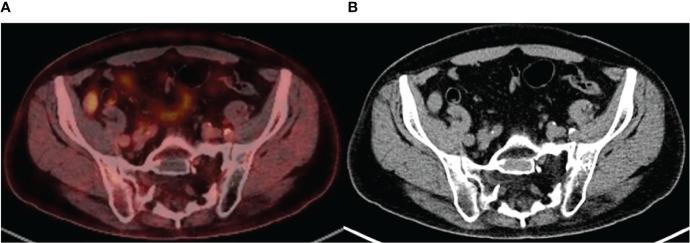

https://cdn.ncbi.nlm.nih.gov/pmc/blobs/a990/9294166/71b58ce83919/fonc-12-936993-g001.jpg